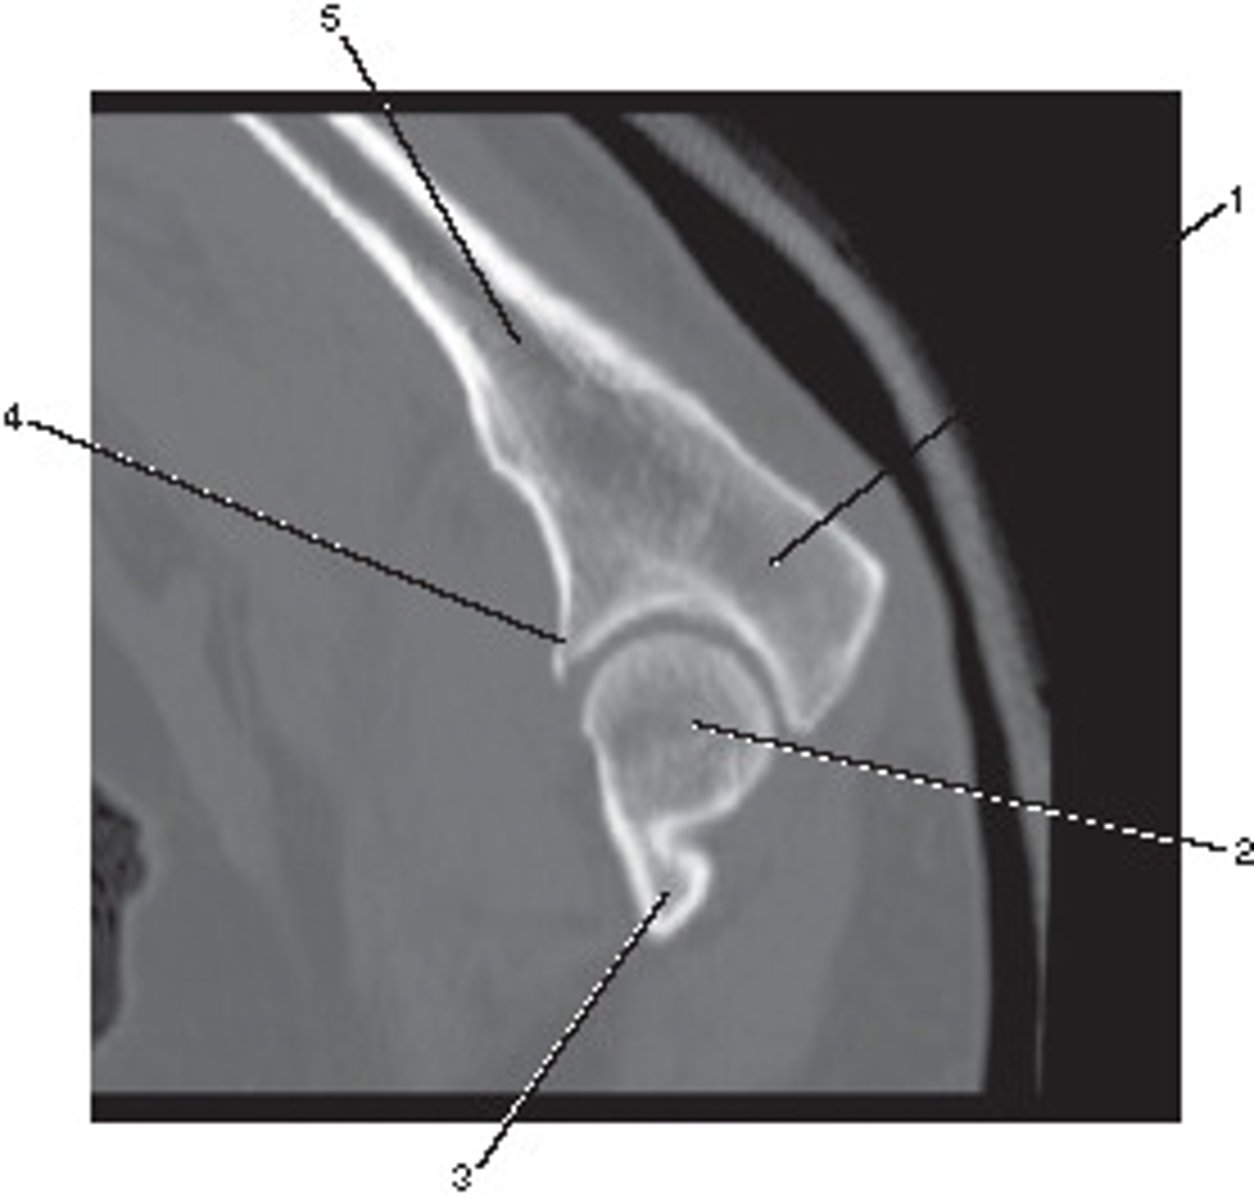

Fibula

Number 1 corresponds to which of the following?

<p>Number 1 corresponds to which of the following?</p>

Lateral Condyle

Number 4 corresponds to which of the following?

<p>Number 4 corresponds to which of the following?</p>

Talus

Number 2 corresponds to which of the following?

<p>Number 2 corresponds to which of the following?</p>

High Spatial Frequency

What type of algorithm would be best suited to demonstrate the bony details of this shoulder?

<p>What type of algorithm would be best suited to demonstrate the bony details of this shoulder?</p>